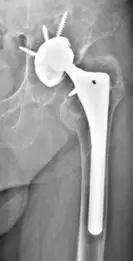

图1,75岁,女性患者,23年前因“双髋发育不良并骨关节炎”行双侧全髋关节置换术,术后恢复良好;右侧内衬磨损,行右侧髋关节翻修术(更换内衬和股骨头);左髋无痛,功能可。